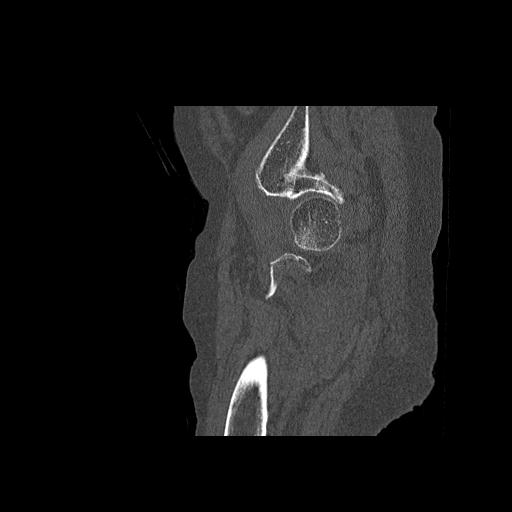

49554 3/13 膝 4R 3/16 4R 1/18 2R 78歳男性 膝蓋骨骨折